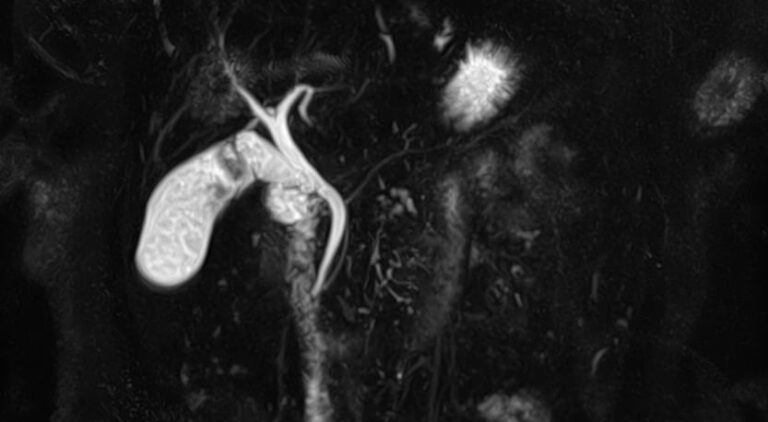

Современным методом обследования для диагностики заболеваний поджелудочной железы является магнитно-резонансная томография. В клинике «Доступная медицина» МРТ поджелудочной железы проводится на новейшем высокопольном томографе экспертного уровня TOSHIBA VANTAGE TITAN 1,5 Тесла, который позволяет получать послойные изображения исследуемой зоны с высокой степенью разрешения. Для лучшей визуализации и выявления минимальных изменений в органе применяется контрастное усиление путем внутривенного введения гадолиниевого контрастного препарата (Магневист, Гадовист, Омнискан и др).

С помощью компьютерного моделирования аппарат создает объемные изображения превосходного качества. Возможности аппарата позволяют поставить точный и достоверный диагноз, что дает возможность выявлять заболевания на ранних стадиях и назначать своевременное лечение.